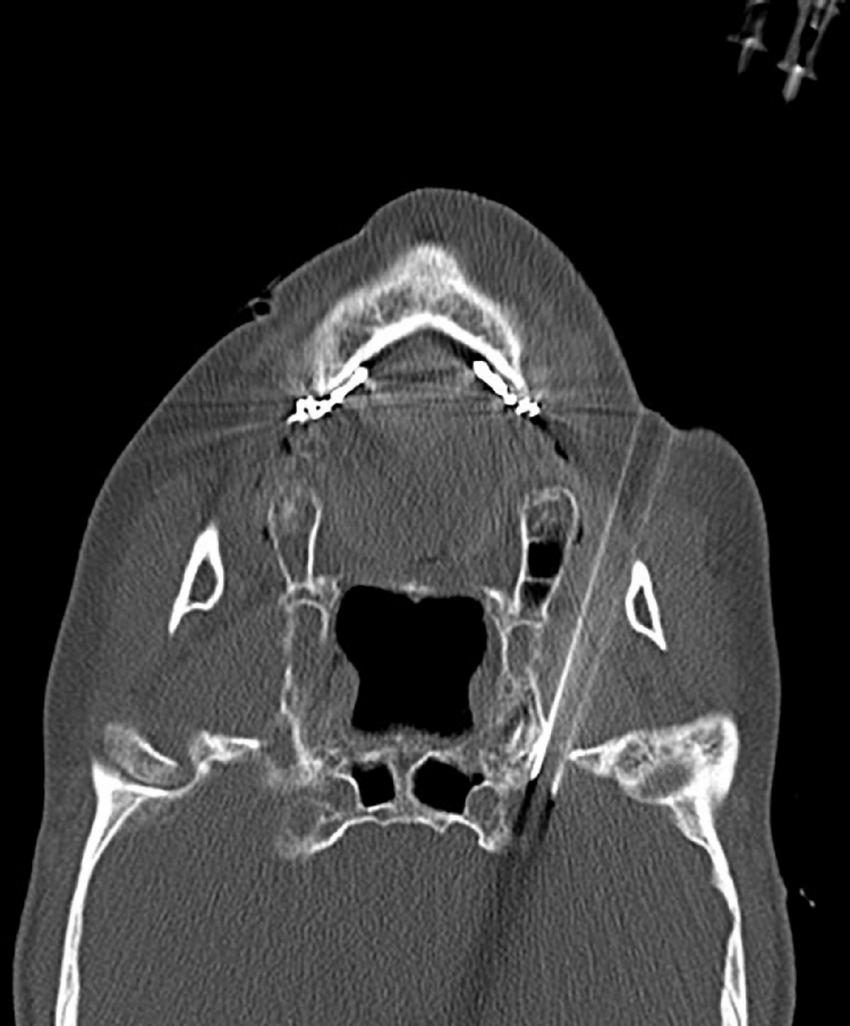

The assumption was that CT scanning revealed the horizontal transverse diameter of the foramen oval on the affected side to be greater than 6 mm. In that case, double-needle bipolar RF ablation technology was used (Huang et al., 2019a): Two parallel puncture paths were designed with the inner and outer sides of the foramen oval as targets, respectively, and an RF needle was punctured into the inner and outer sides of the oval foramen along the designed path to the internal opening of the oval foramen. Double-needle bipolar radiofrequency ablation was performed after satisfactory electrophysiological testing (Figure 5).

FIGURE 5

Two puncture needles are inserted into the foramen ovale.